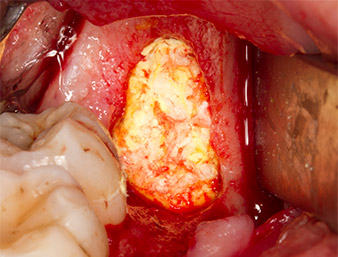

The tissue above the root remnant was not completely ossified and consisted for the most part of granulation tissue modified by inflammation (Fig. 4).

To obtain autogenous material for subsequent wound treatment, healthy bone chips were harvested from the surroundings of the root remnant with a piezo surgical instrument (Piezomed B5) (Fig. 5).

The autogenous tissue was removed with the scraper-shaped section of the working part of the instrument and stored in a physiological saline solution until further use (cf. Fig. 13).

Periapical inflamed tissue was also removed very carefully with a manual excavator. Fig. 12 shows the empty alveole with exposed inferior alveolar nerve.

Subsequently, the autogenous bone tissue (Fig. 13) was placed into the alveole and the surrounding bone defect (Fig. 14). Collagen fleece covered the bone chips up to bone level as protection for the exposed nerve (Fig. 15). Sutures using vicryl thread, USP 4.0, were used to close the opened up soft tissue (Fig. 16). An Ibuprofen preparation (Seractil 400 mg, 3x1) and an antibiotic consisting of amoxicillin and clavulanic acid (Augmentin 1 g, 2x1) were prescribed postoperatively.